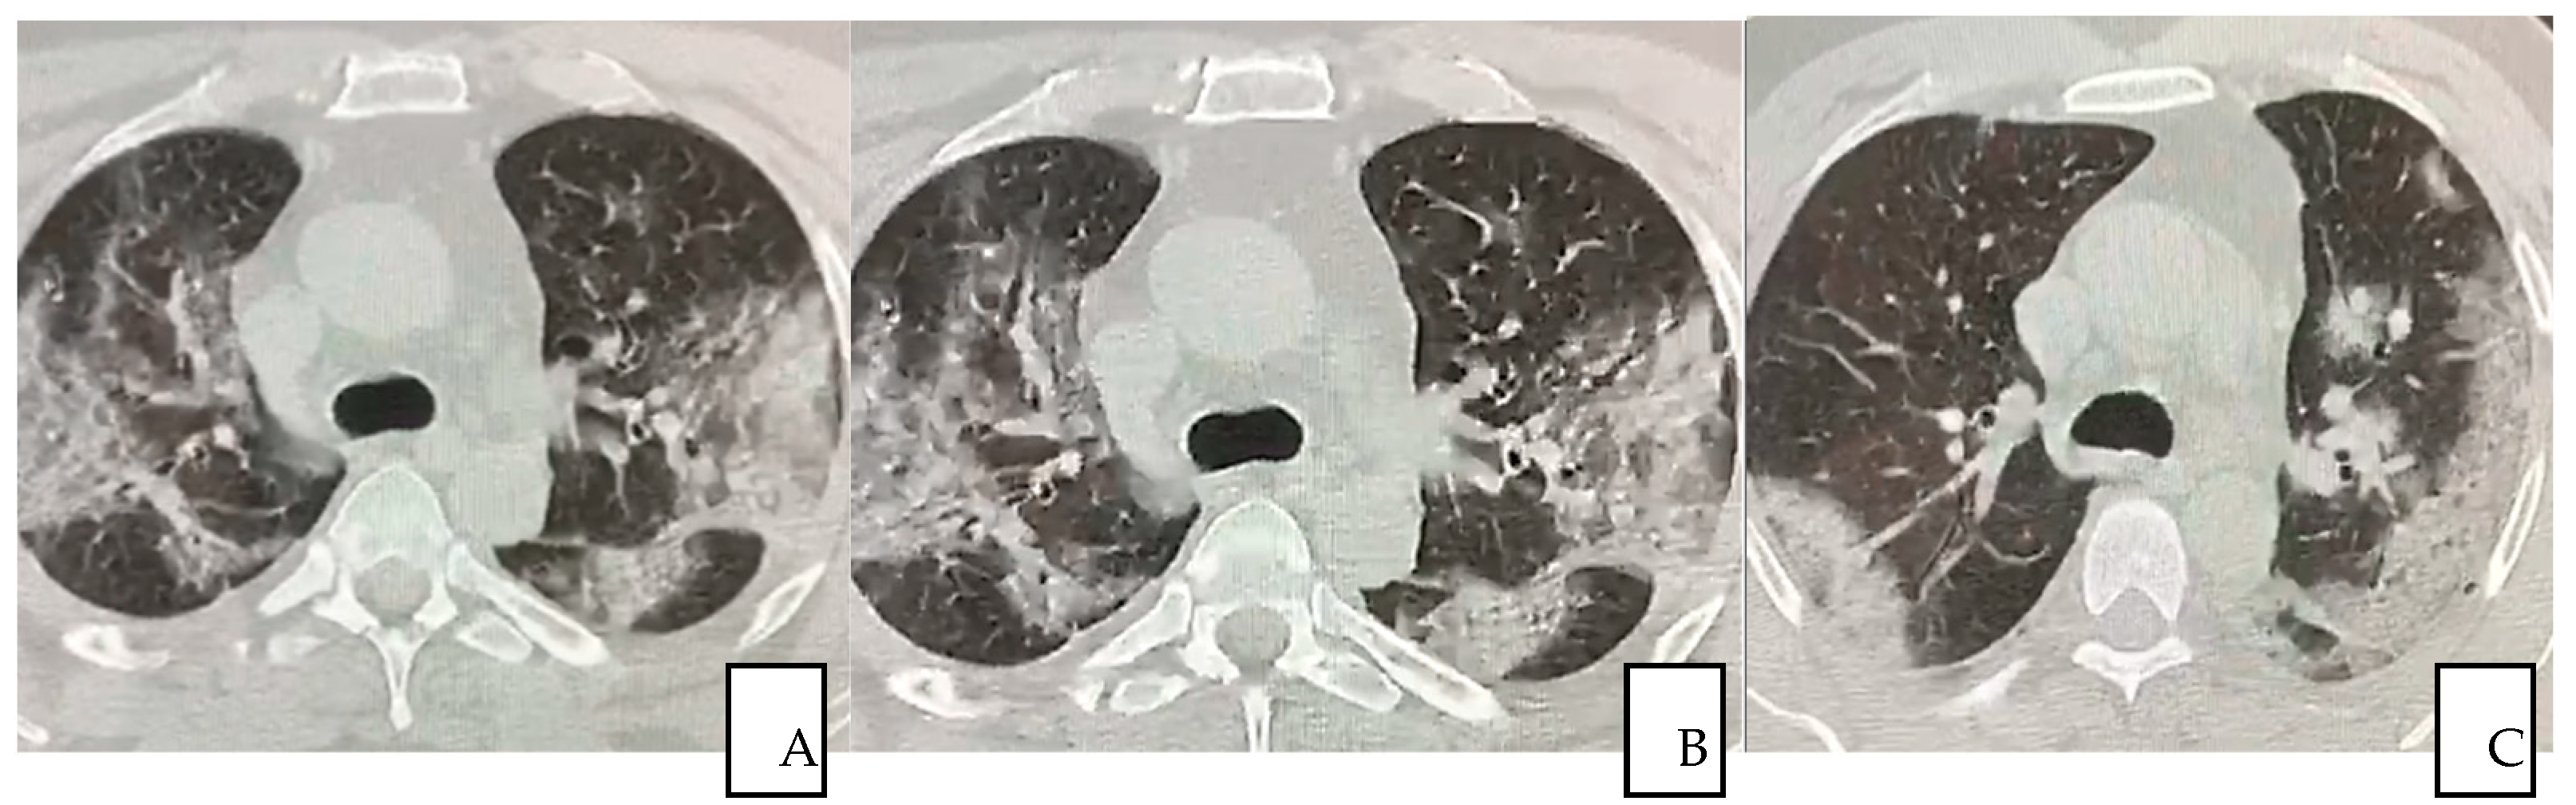

The first pulmonary high-resolution computed tomography (HRCT) scan at the admission on November the 18th revealed extensive bilateral damages as shown in Figure 1A–F. The CT scan results at the time of the admission often confirmed severe deteriorated lung structures and functionality.

Figure 1.

(A–F) A 56-year-old man presented with fever for 3 days, accompanied by anuria, asthenia, general malaise and positive to COVID-19 (A–E) Pulmonary HRCT obtained on 18 November 2020 showed multiple peripheral patchy ground glass opacities bilaterally being the lower lobes the most involved areas in (F).